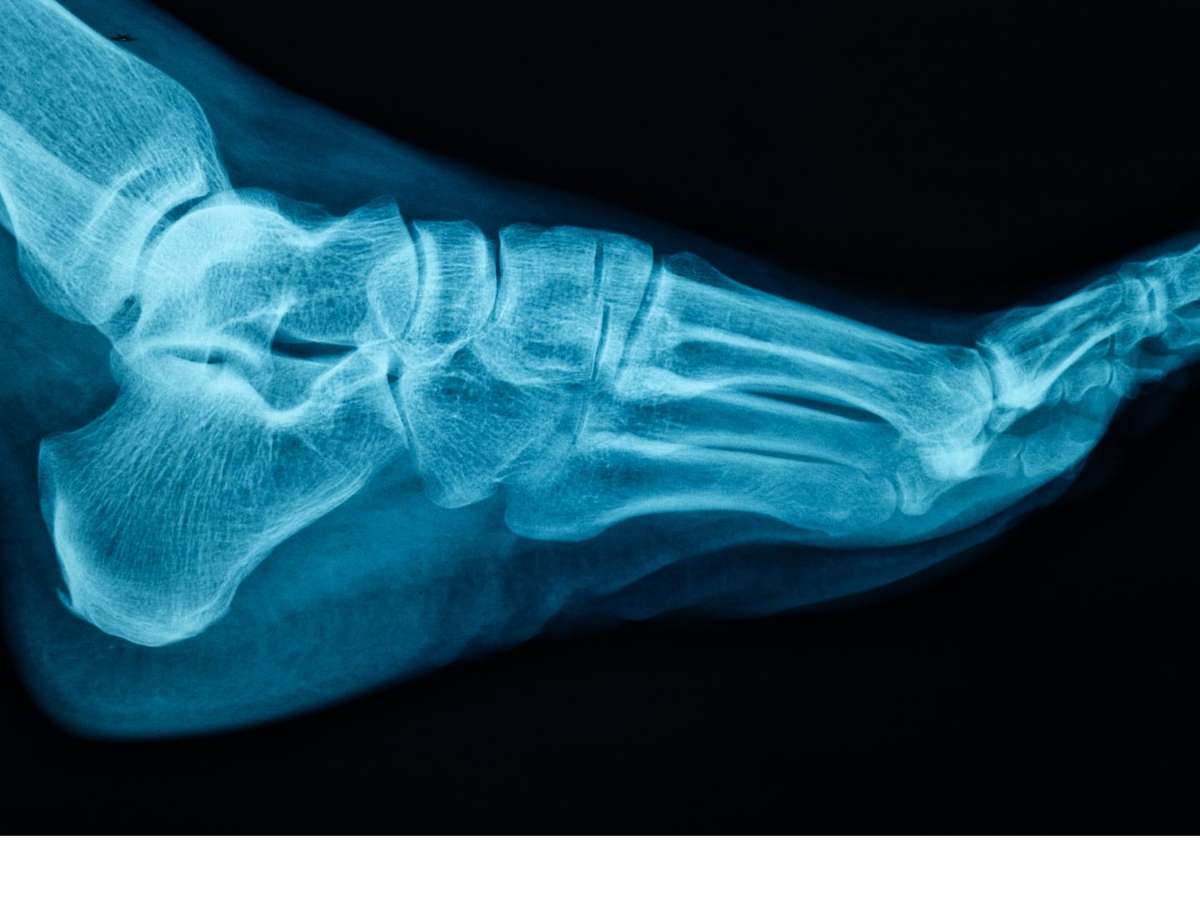

As intervenções cirúrgicas na região do pé são, em sua maioria, motivadas por traumas, desgastes e condições adquiridas, como o joanete e o pé plano

As intervenções cirúrgicas na região do pé são, em sua maioria, motivadas por traumas, desgastes e condições adquiridas, como o joanete e o pé plano. Sanhudo, que também atua no desenvolvimento de dispositivos médicos com a NeoOrtho, destaca que o uso de calçados inadequados é um dos grandes vilões da saúde ortopédica. Escolher sapatos que não oferecem estabilidade e amortecimento pode desencadear dores não apenas nos pés, mas também nas pernas e na coluna. "É fundamental escolher sapatos que ofereçam uma combinação de estabilidade e amortecimento eficaz para absorver o impacto e proporcionar estabilidade durante a marcha", explica o médico. O ajuste deve ser perfeito desde o início para evitar bolhas, calos e insegurança ao caminhar.